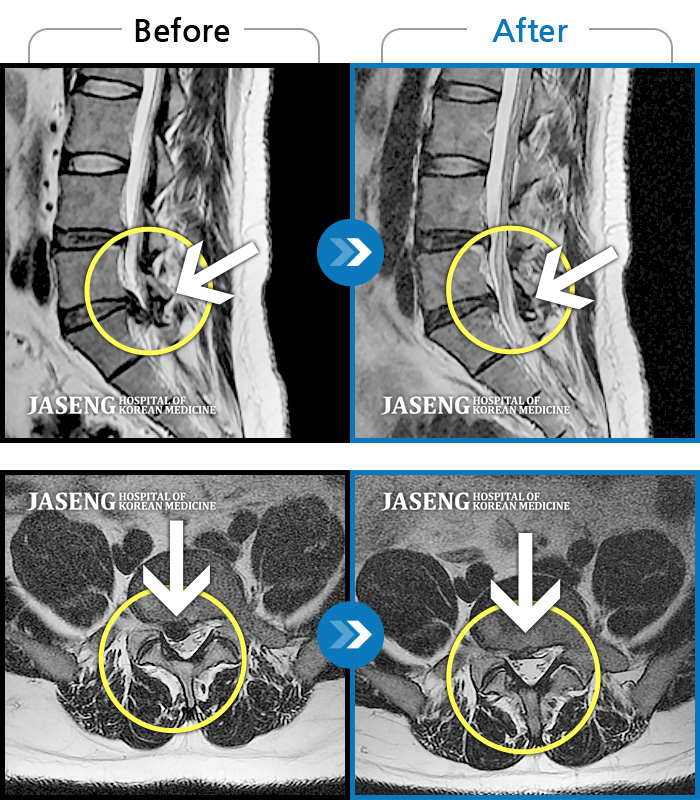

허리디스크

부천 · 신동재 원장

양쪽 허리와 골반 통증, 걸을 때 우측 다리 당김 및 통증

촬영시기

2018.04.27 ~ 2019.02.01

2019.02.21

조회수 3,542